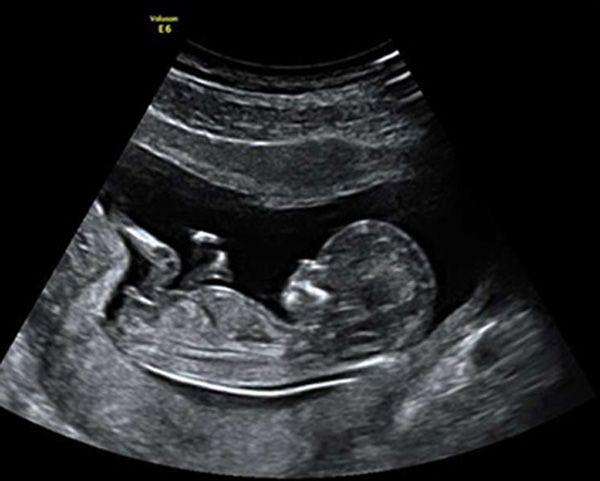

En gennemscanning af barnet fra uge 14+0

Ved valget af denne type scanning laves en gennemscanning af barnet, hvilket udføres i henhold til anvisninger fra DSOG (Dansk Selskab for Obstetrik og Gynækologi).

Under scanningen ser vi på flere af barnets organer, herunder bl.a. hjerte, nyrer og blære. Barnets hoved, mave og lårbensknogle måles og der ud fra laves en vækstberegning. Vi ser også på barnets arme, ben og føddernes rotation, rygsøjle og mellemgulv samt antal kar i navlesnoren. Vi kigger efter læbespalte og ser på begge øjenhuler og øjenæbler. Moderkagens placering ser vi også på og vi hører barnets hjerte. Ønsker I at kende barnets køn, kigger vi naturligvis også efter det.